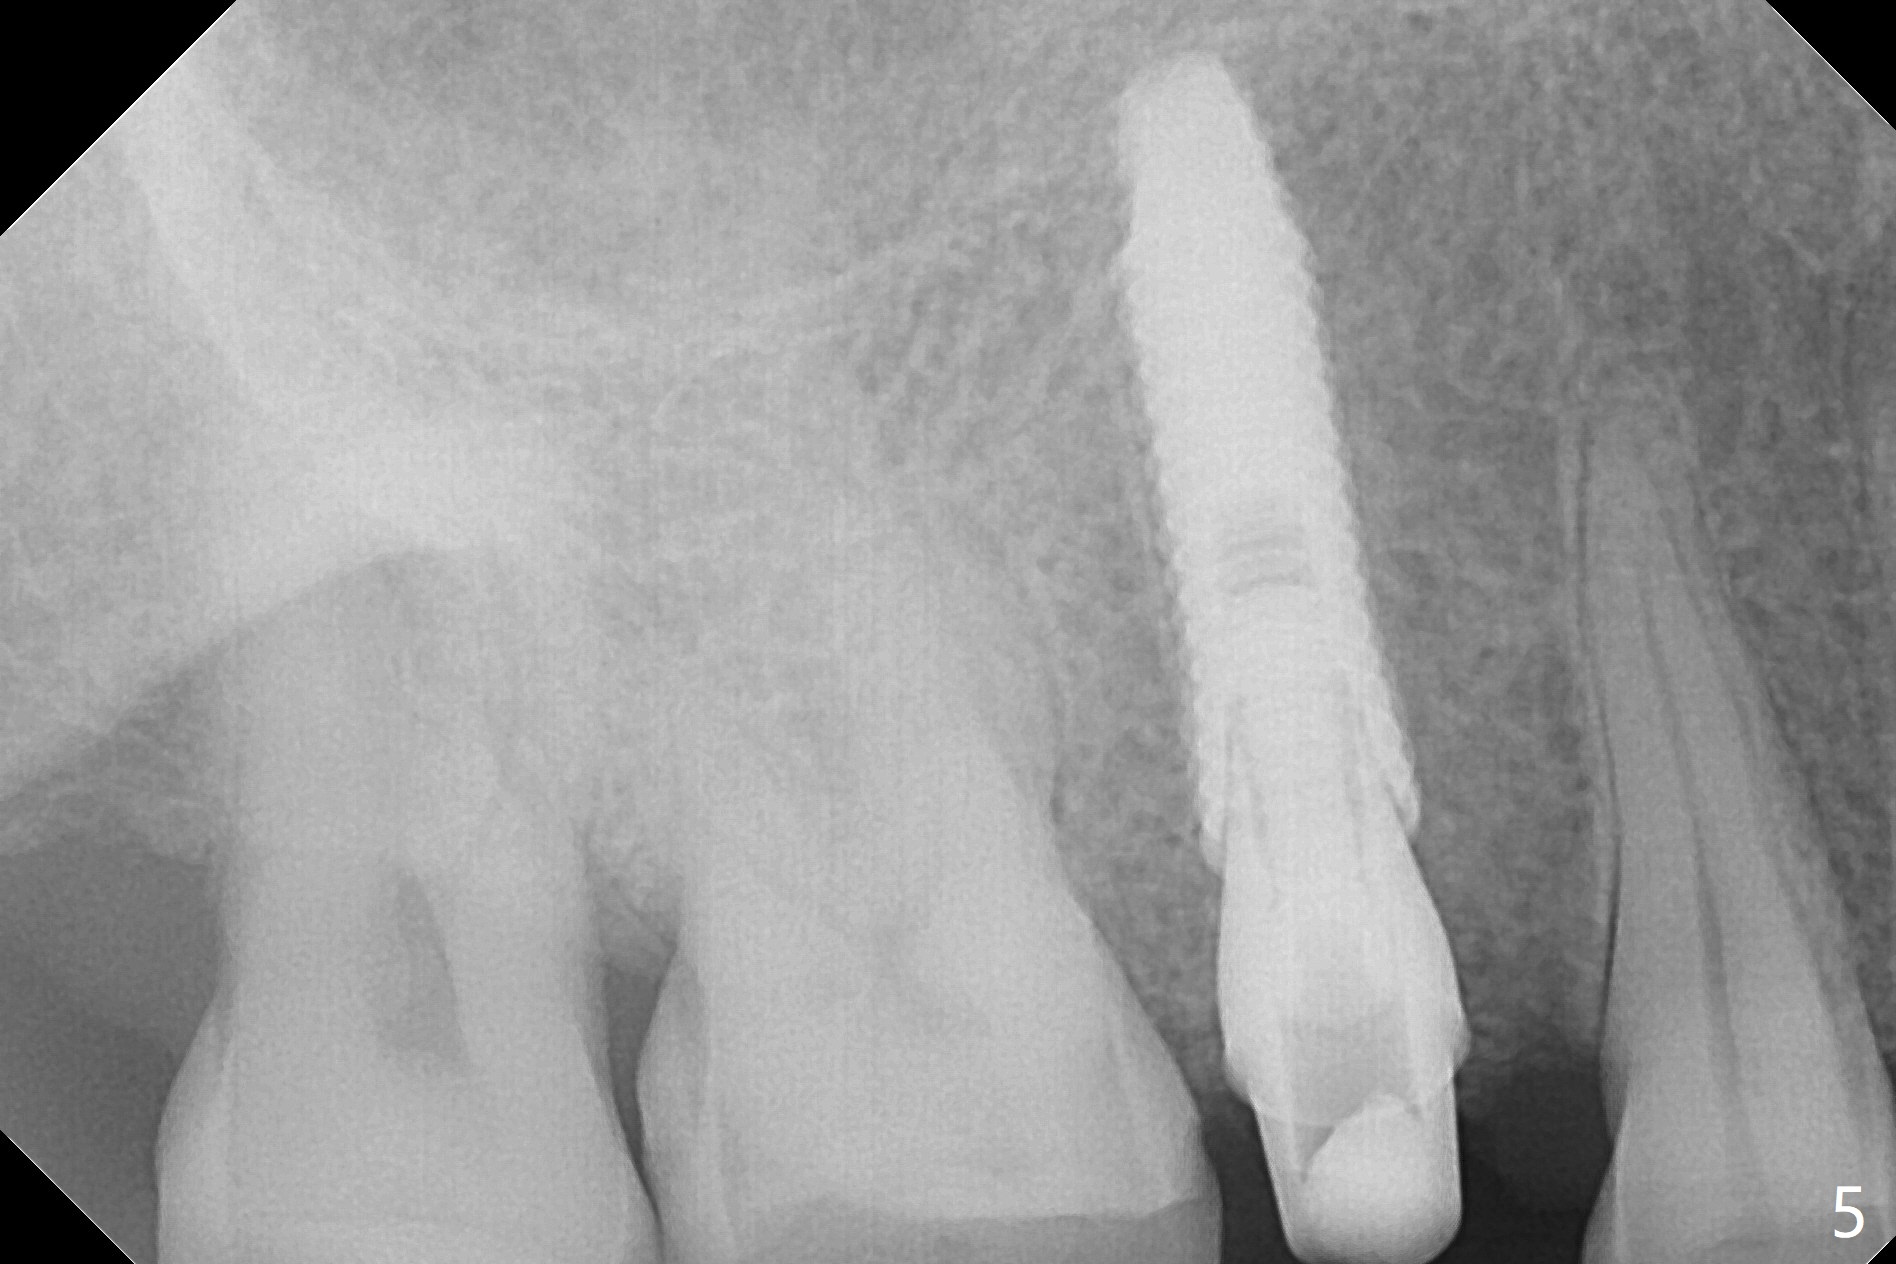

After sequential osteotomy, a 4x16 mm implant is initially unable to be seated low enough for the buccal crest. Following packing the osteotomy with Vanilla Graft (.5-1 mm) and additional 2-3 mm depth of osteotomy with 3 mm reamer, the implant is placed slightly apical to the buccal crest (Fig.4,5, ~35 Ncm); with placement of Vanilla Graft (*) and a 4.5x4(4) mm abutment, an immediate provisional is fabricated to close the socket. In fact the long implant has not penetrated the sinus floor (Fig.8 (from panoramic X-ray)).